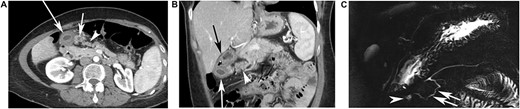

The radiological presentation of the developmental anomaly was similar in all cases, as described in Table 1. The presence of a duplicated pancreatic head was visible on both CT (Fig. 2A and B) and MRI (Fig. 2C). This accessory pancreatic parenchyma was connected to the pancreatic head on one side and a gastric duplication in the pyloric part of stomach on the other side (Fig. 1). It was seen as a small band, 1 cm in diameter, of pancreatic parenchyma with the same density or signal as the adjacent normal pancreas. The band was continuous with the anterior part of the head of the pancreas and then clearly separated, going toward the stomach in an anterior and cranial direction. A pancreatic accessory duct draining this duplicated pancreatic head and connected to the gastric duplication was seen in half of the cases on CT, and was always seen on MRCP (Fig. 2C).

CT findings in a 49-year-old female patient who had 11 episodes of acute pancreatitis during 20 years. CECT performed 4 months after the occurrence of the last episode of pancreatitis showing an additional elongated pancreatic tissue, ahead of normal pancreas (arrowhead). (A) An additional elongated pancreatic tissue, ahead of normal pancreas (arrowhead) and two cysts are seen, under the pyloric part of stomach, very close to the heterotopic pancreas, the large cyst (long white arrow) was the gastric duplication, the small cyst (short white arrow) was a small abscess residue. (B) In this case, on this coronal view, the stomach was located over the gastric duplication (black arrow) and the duplicated pancreatic parenchyma (white arrow head), containing a duct, is clearly separated from the normal pancreatic parenchyma, associated with the gastric duplication cyst (long white arrow). (C) Magnetic Resonance Cholangio-Pancreatography (MRCP) points out the cystic lesion under the pyloric part of stomach (arrowhead), connected to a pancreatic accessory duct in a duplicated pancreatic head (white arrow), which is connected to the main pancreatic duct.